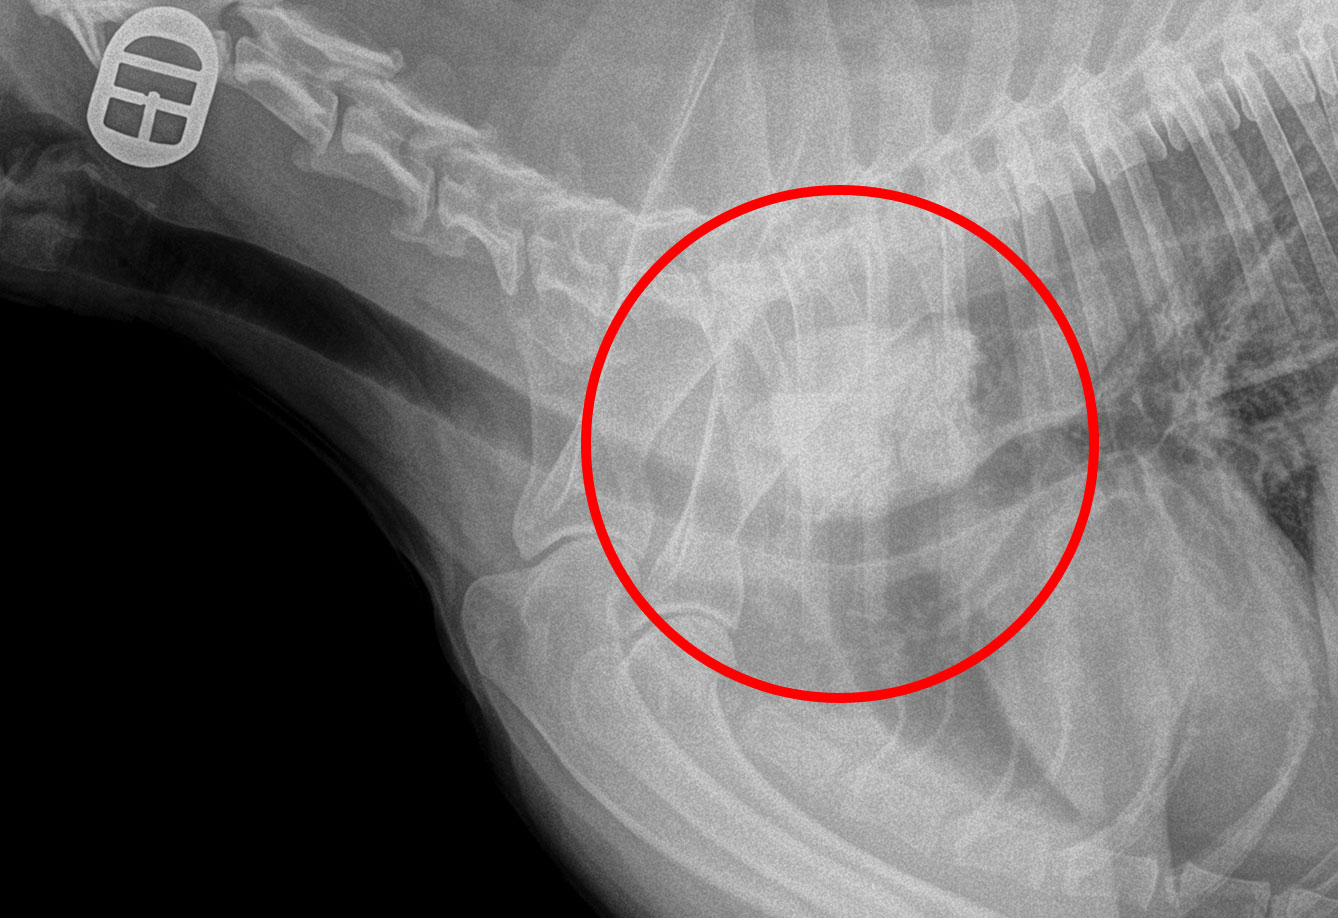

From www.brisbanepetsurgery.com.au

Oesophageal Foreign Bodies in Dogs, Treatment and Cost in Brisbane Pocket In My Esophagus The cause of zenker's diverticulum. These are pockets in the throat at the top of the esophagus and behind the upper esophageal sphincter, a valve at the upper end. It’s a pouch that forms at the bottom of your throat where your throat connects to your esophagus. If it grows large enough, it can cause a range of symptoms. Rarely,. Pocket In My Esophagus.